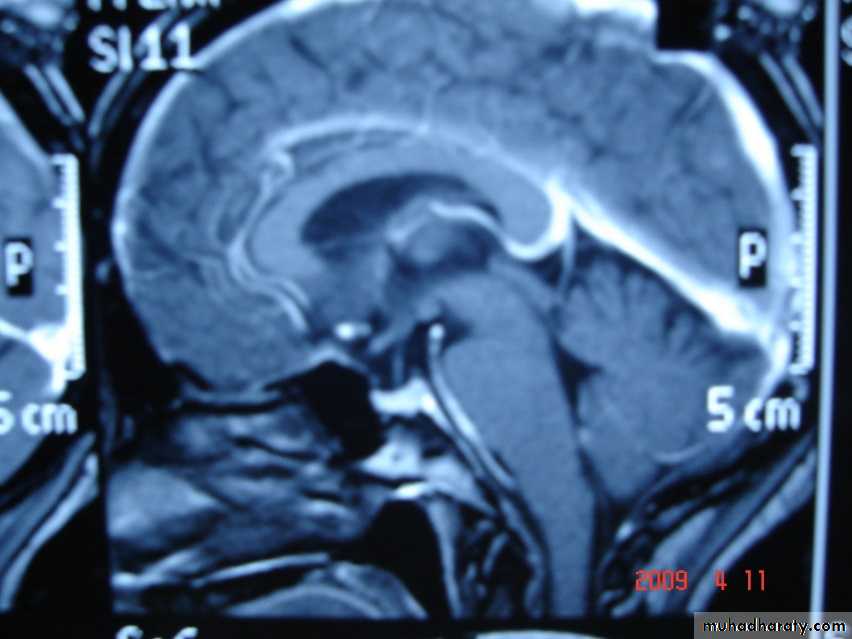

Sagital section of brain ( T1 w post contrast injection)

AQUIDUCT STENOSIS: It is the most common cause of NON- Communicating Congenital hydrocephalus , it is congenital obstruction or stenosis of the aqueduct which result in hydrocephalus involving the 3rd & lateral ventricles.

ARNOLD CHIARI MALFORMATION

1-Donward herniation of cerebellar tonsil & medulla oblongata beneath level of foramen magnum.

2- elongation of 4th ventricle.

3- associated with aqueduct stenosis.

4- associated with myelomeningocele.